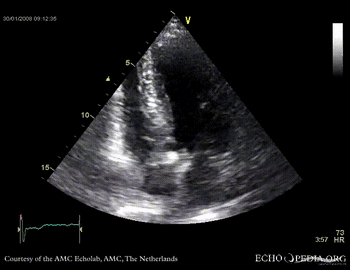

Aortic valve stenosis

AoS6